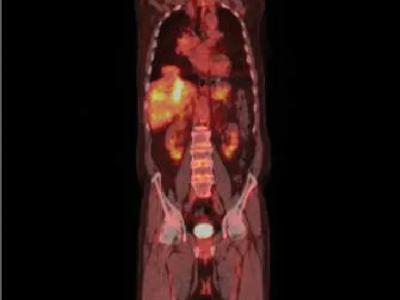

GCA patients with AORTITIS proven by CTA or FDG-PET/CT have higher rates of relapse. Among 82 GCA pts, 78% positive on b

Tweet Content

GCA patients with AORTITIS proven by CTA or FDG-PET/CT have higher rates of relapse. Among 82 GCA pts, 78% positive on both CTA & PET. Relapse was seen in 70% in the CTA+/PET+ group & 29% in the CTA-/PET+ (p = 0.019). https://t.co/2zU9ueWkEZ https://t.co/aFn2xH6KmI